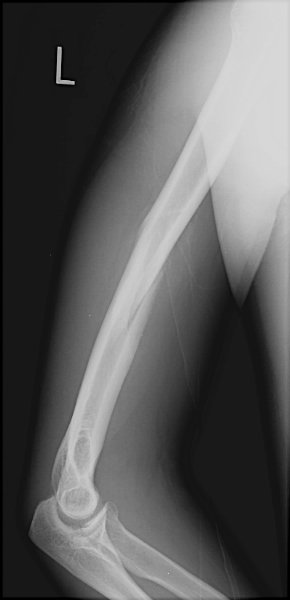

Return to Humeral Shaft Fracture